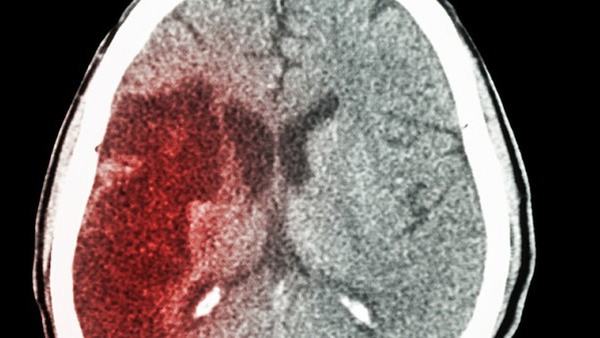

其次,老年脑萎缩主要表现为脑容量减小,大脑皮质变薄,并伴随着与认知相关的问题,如记忆力下降、思维迟钝等。小脑萎缩主要影响小脑,导致小脑体积缩小,进而影响身体运动和平衡控制。患者可能会出现手臂和腿部肌肉无力、协调障碍、共济失调等症状。

综上所述,老年脑萎缩和小脑萎缩是不同类型的脑部退化疾病。老年脑萎缩主要表现为大脑的退化和与认知有关的问题,而小脑萎缩则主要影响小脑,导致运动和平衡控制异常。虽然二者有一些相似之处,但由于发病原因、症状表现和治疗方法不同,需要根据具体情况进行正确的诊断和治疗。